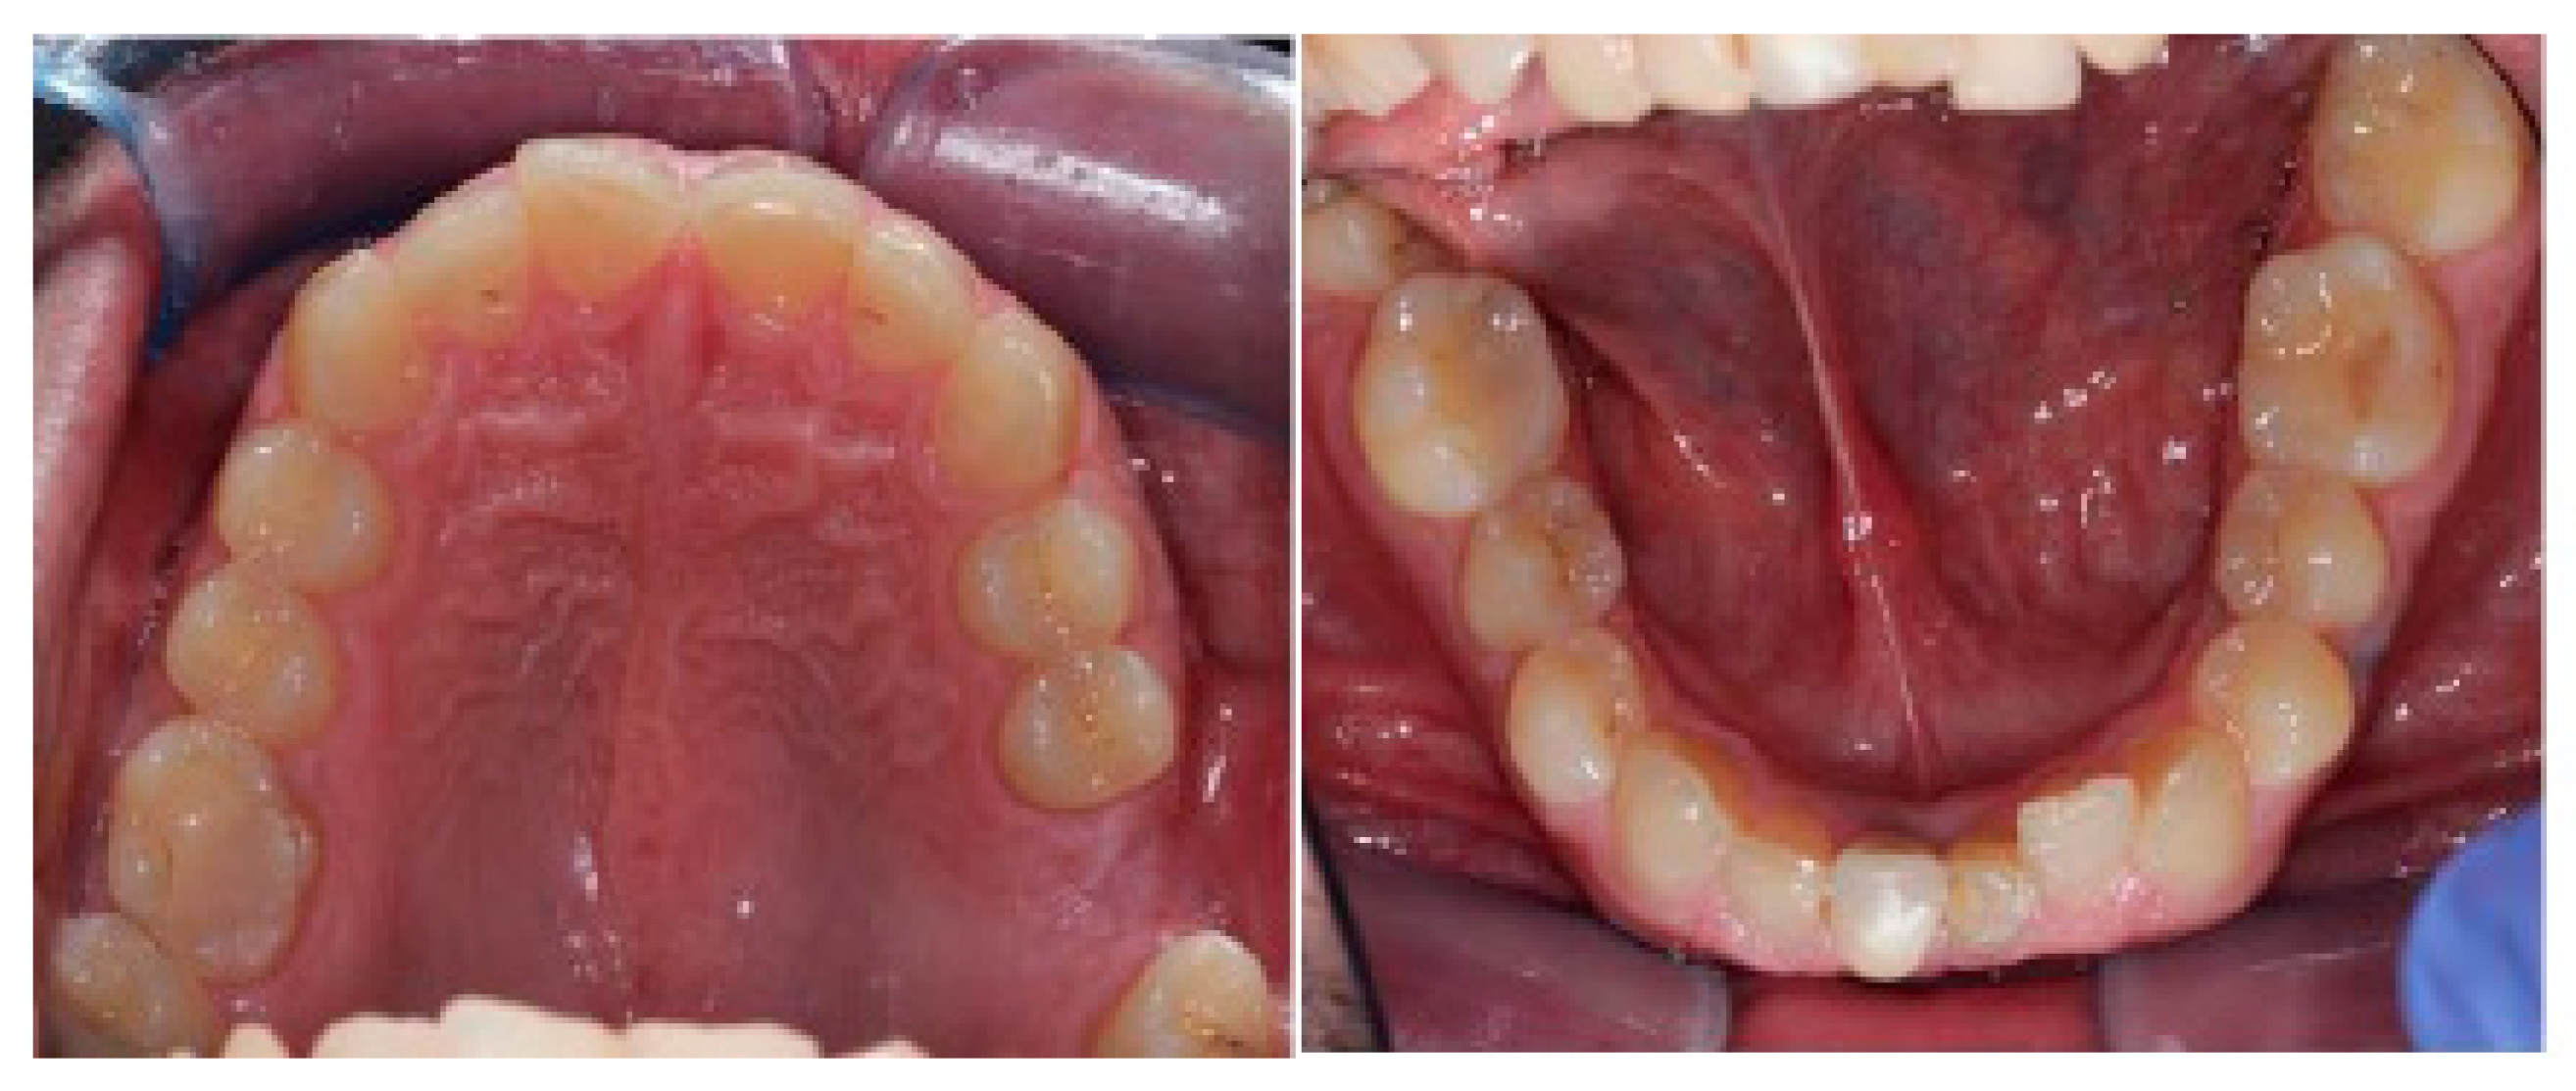

The occlusal relationships are shown in Figure 3.

Intraoral occlusal relationships are shown in Figure 16.

Figure 3. Occlusal relationships.

Figure 16. Intraoral photos and intraoral scans show occlusal relationships: class I molar on the right and left and lower midline deviated to the right compared with the upper.